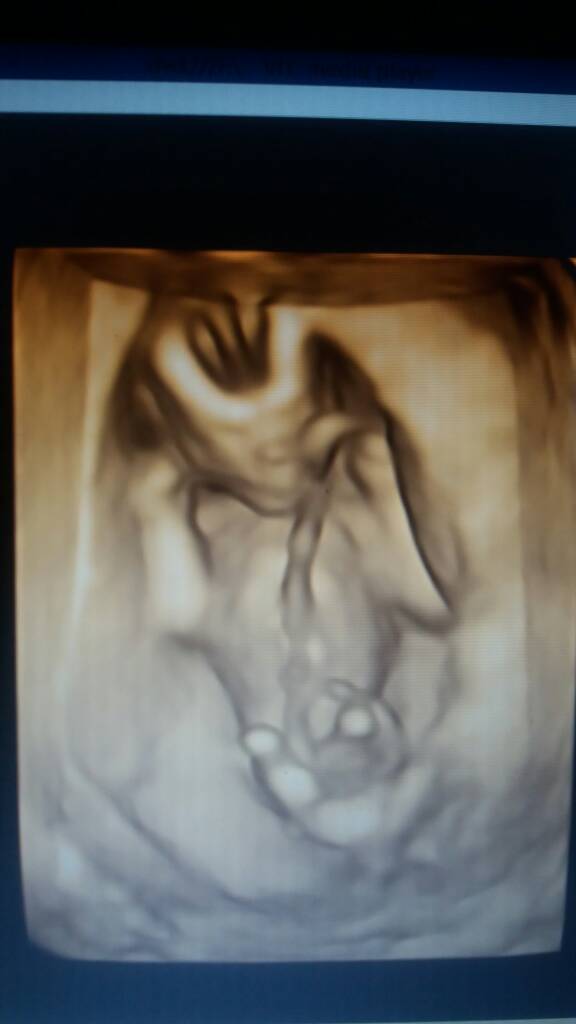

O boze jakie cudo!!!Ja jutro bede siedzieć i czytać Wasze postyna dobranoc jeszcze taka foteczka <3 jestem podeksytowana i zaraz zasne hihi